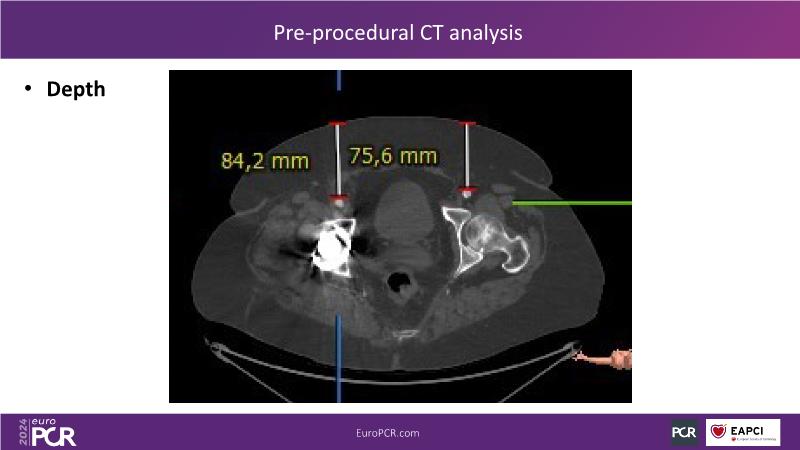

Tune in to this session for insights on optimizing vascular access and closure techniques. Explore steps like thorough CT analysis, ultrasound-guided puncture, and contingency plans for alternative access methods to minimize complications. Discover a novel patch-based closure approach offering immediate hemostasis and simplified usage, addressing issues like re-access associated with other closure technologies. Witness the effectiveness of combining suture- and plug-based closure methods for achieving excellent outcomes.